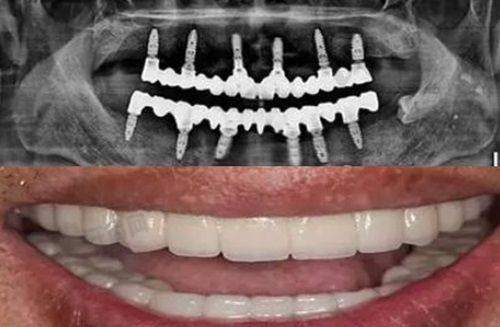

种植牙修复:在种植牙修复方面,池州安美口腔门诊部做得相当出色。它可以进行单颗、多颗种植牙修复,并且合作的种植牙品牌有韩国登腾、美国皓圣、瑞士ITI种植体等,能够满足不同经济条件顾客的需求。其中,韩国种植牙价格相对便宜一些,为经济条件有限的患者提供了更多选择。

陈静医生:陈静医生是种植牙医生,主要开展微创种植牙技术、单颗和多颗缺牙修复。在牙齿修复过程中,她能够灵活运用口腔美学理念,满足患者对于牙齿实用耐用又兼顾美学的需求。这意味着患者不仅能解决牙齿缺失的问题,还能拥有美观的牙齿外观。